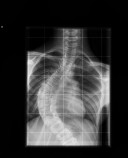

Ismay scoliose

This is picture 1